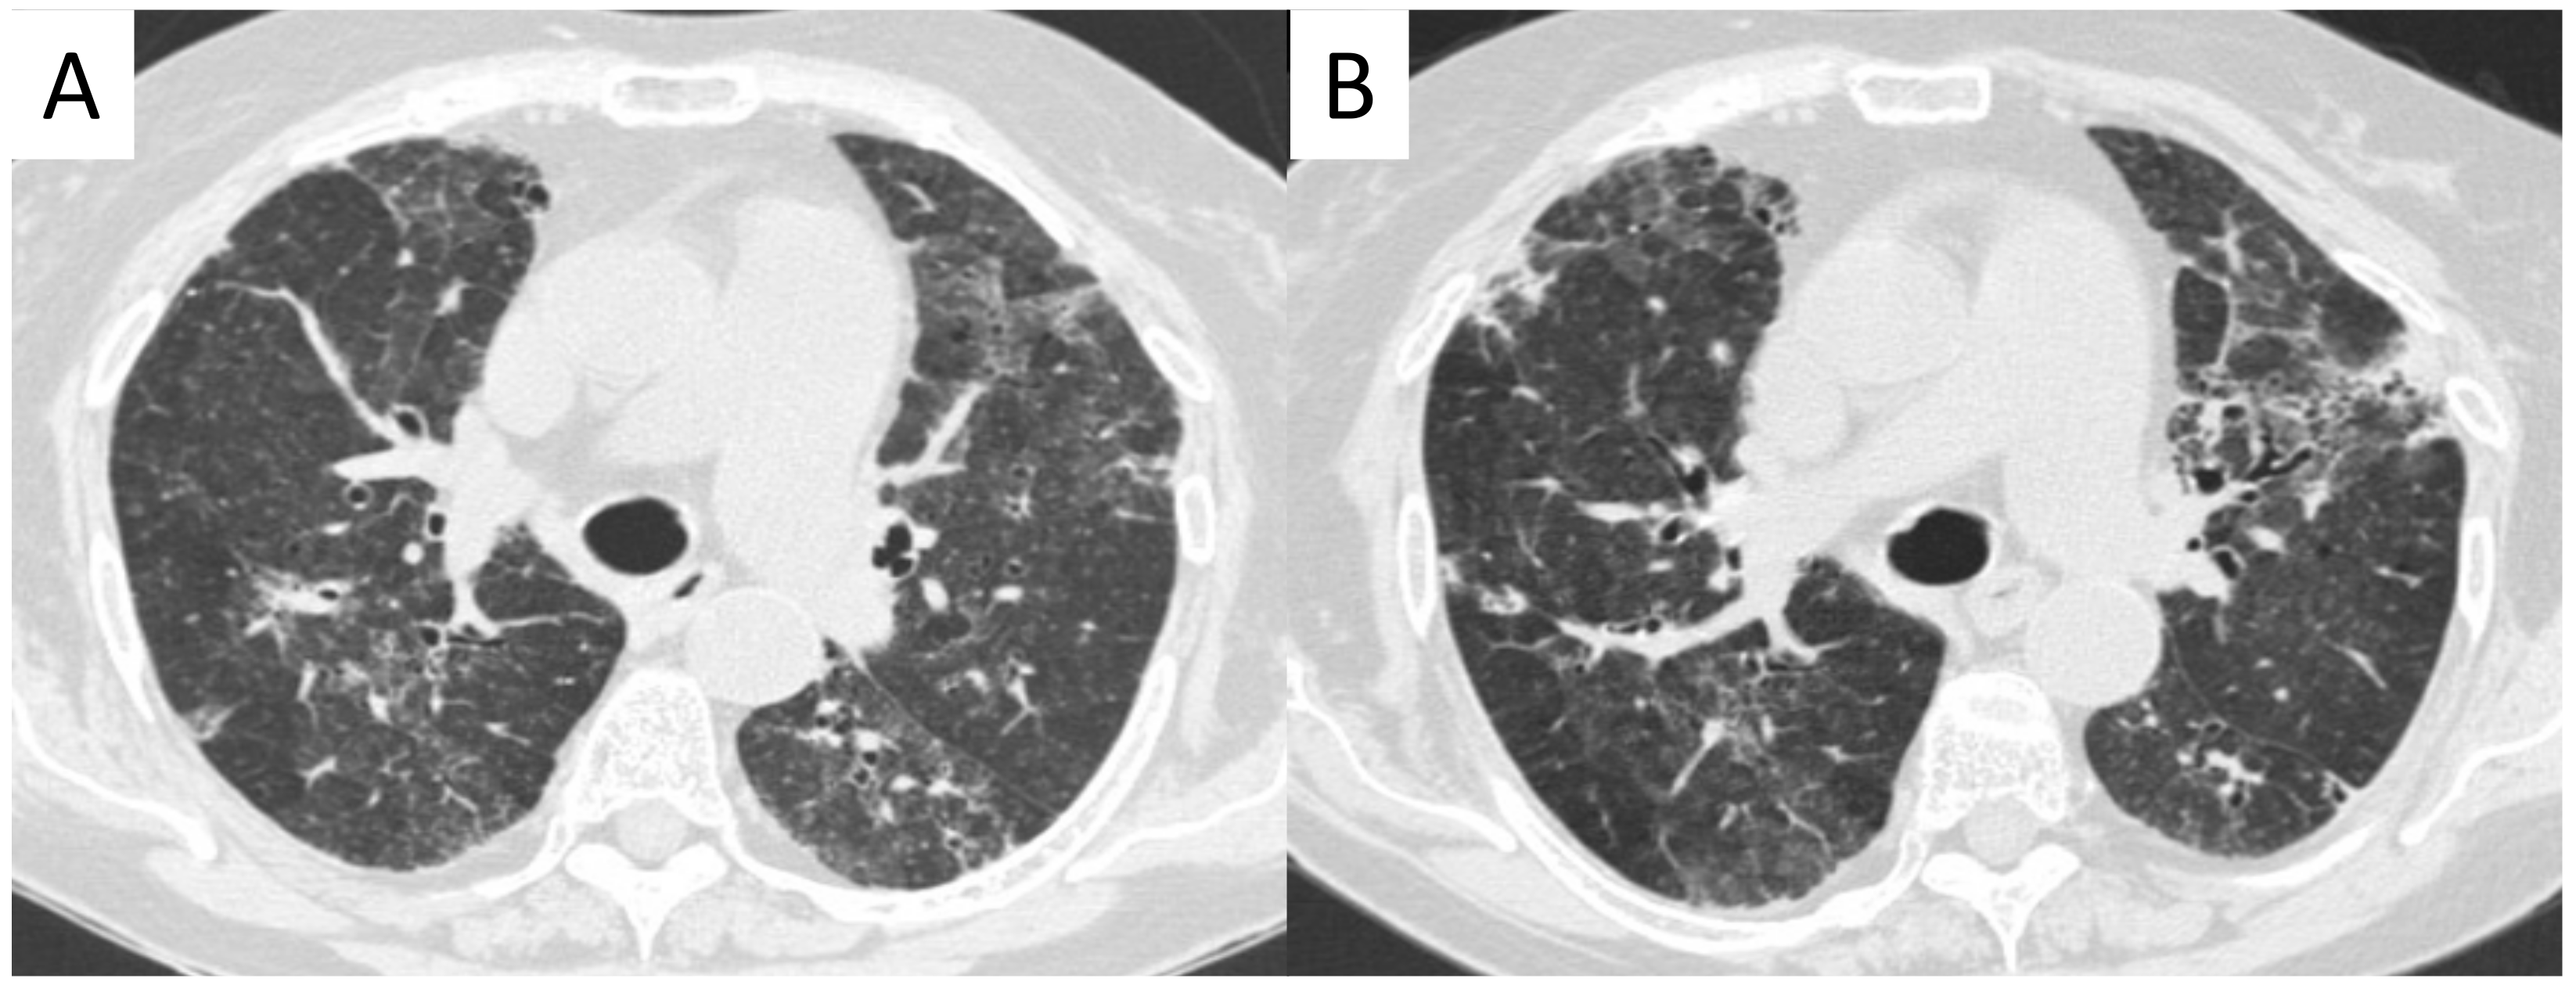

2.3. Microscopic Polyangiitis (MPA)

2.4. Granulomatosis with Polyangiitis (GPA-Wegener’s Disease)

| Vasculitis | HRCT Features |

|---|---|

| MPA | GGOs due to hemorrhagic alveolitis (common); consolidation, nodules with centrilobular distribution (less common) |

| GPA | Solid nodules, GGOs due to hemorrhagic alveolitis (common); halo sign, crazy paving (less common) |